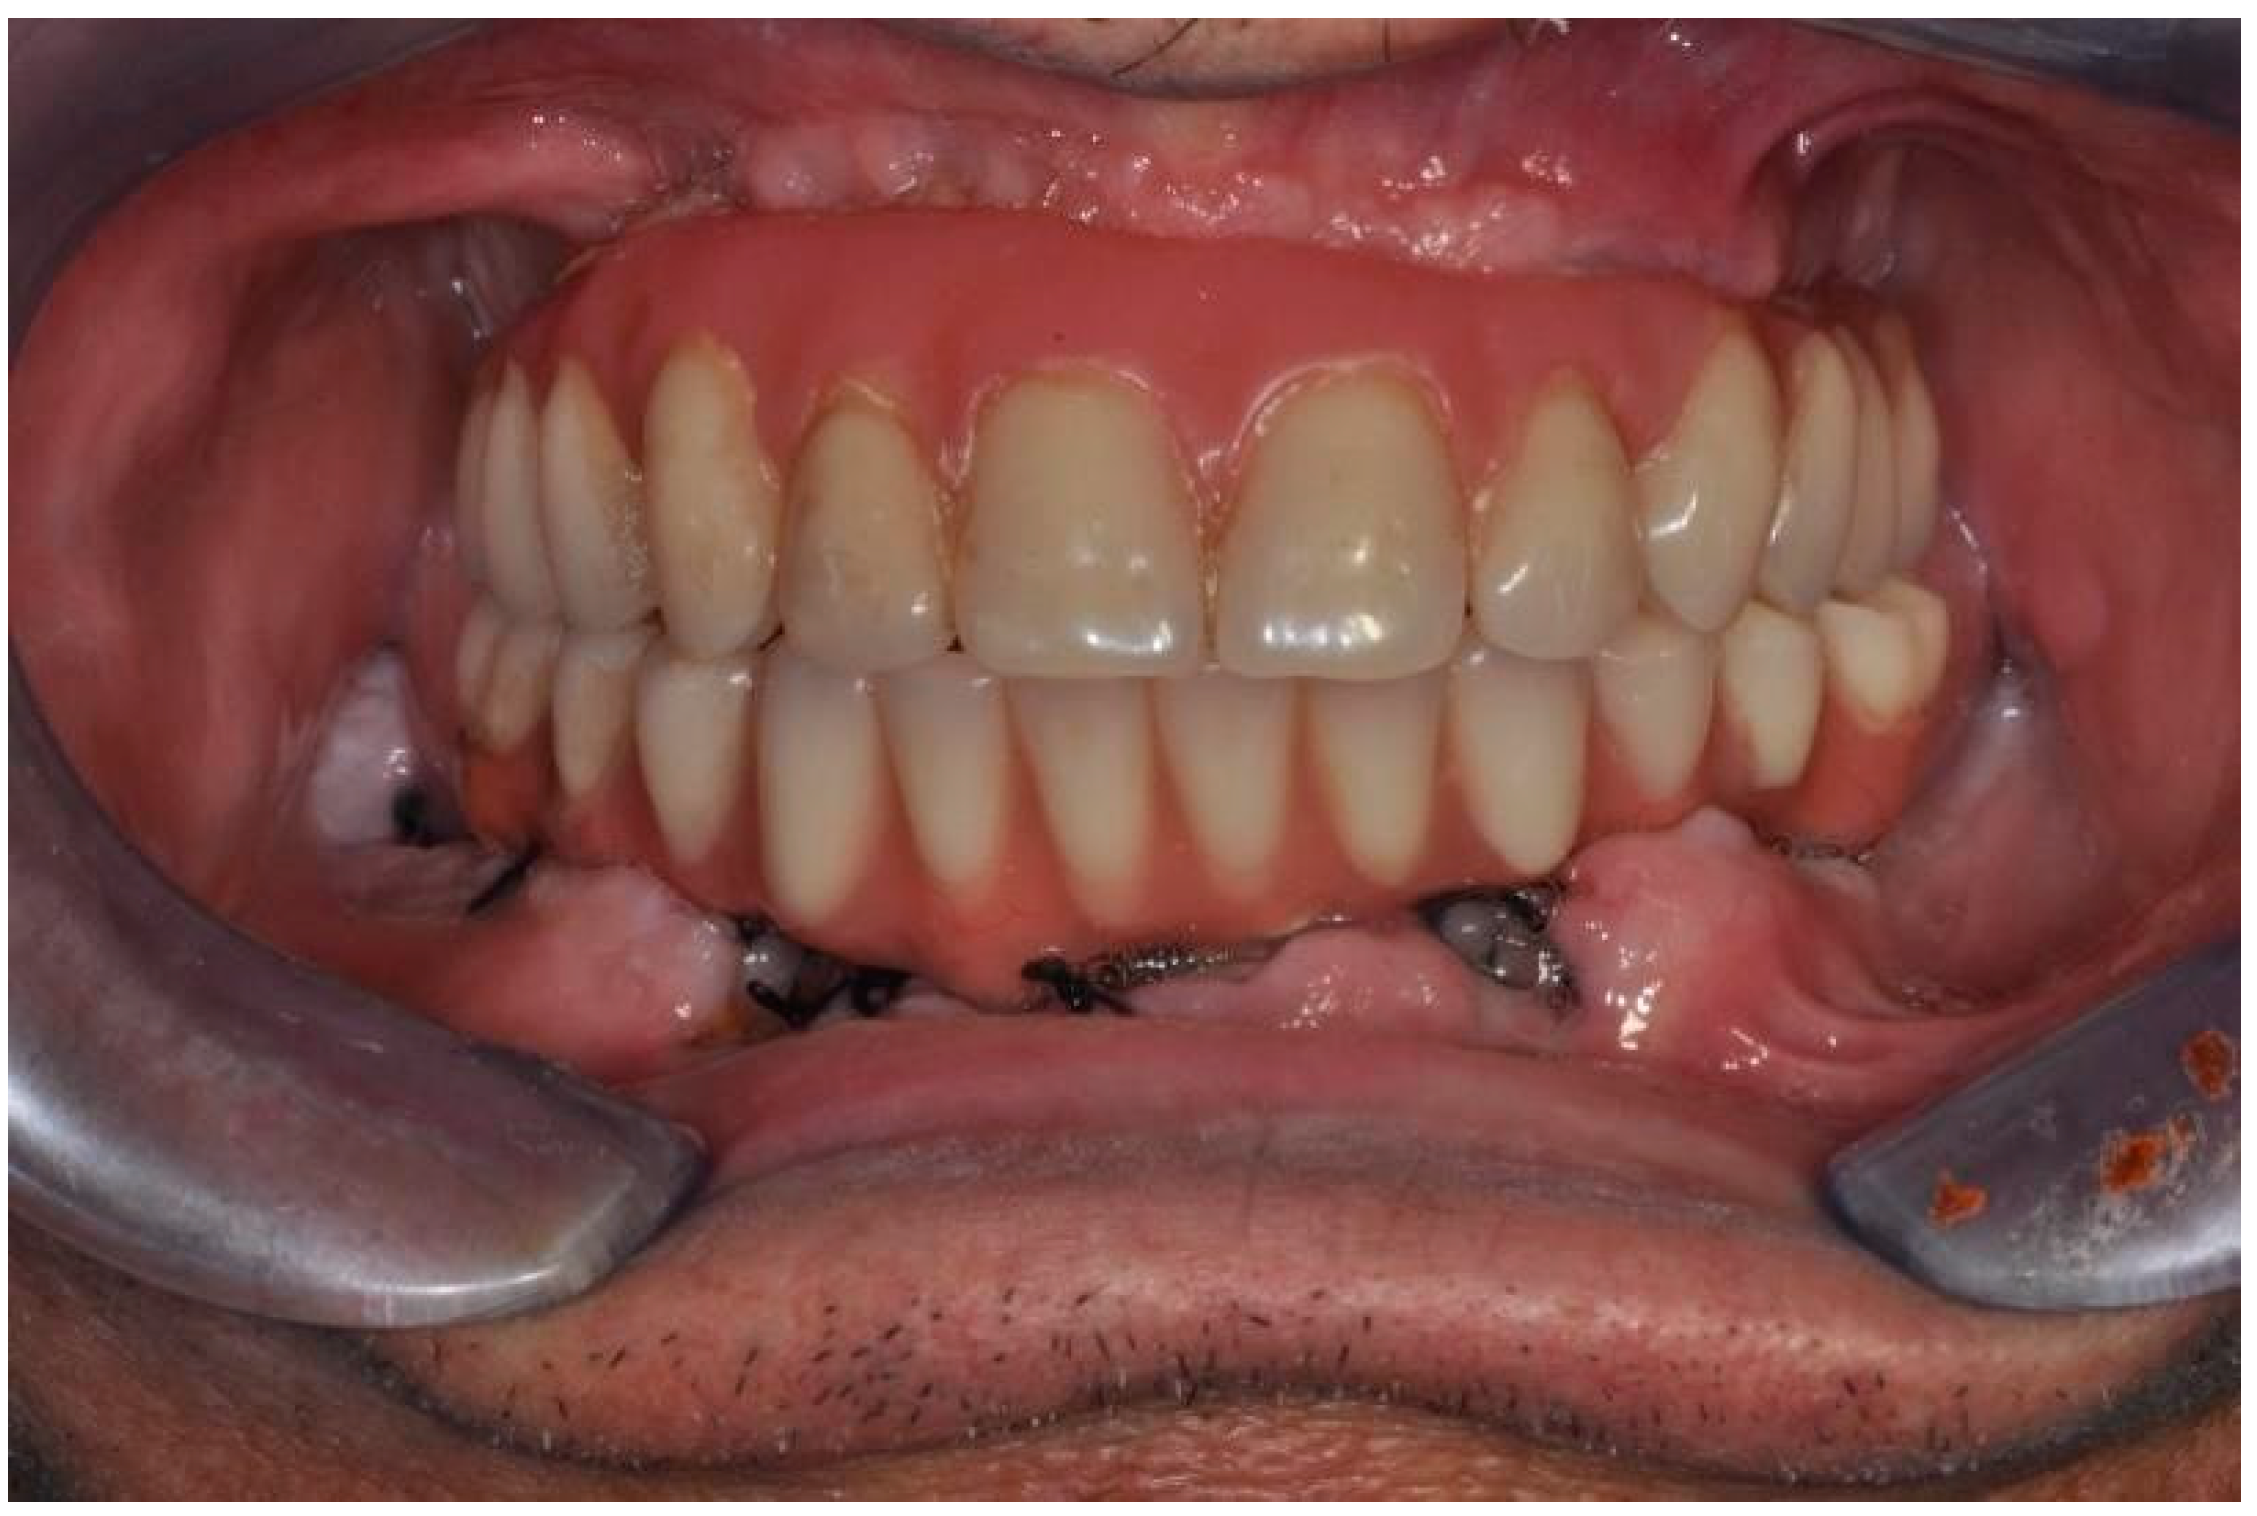

| Flanagan D. et al. [23] | J Oral Implantol | 2015 | clinical and radiographic: full-mouth radiographic series, panoramic and a bimaxillary cone beam computerized scan and mounted study casts | -One patient | Subject of 34 yo male; severely carious teeth and associated chronic abscesses (kidney transplant delayed) Comorbidities: IgA nephropathy, tabagism, hypertension and secondary hyperparathyroidism. Hemodialysis three times weekly. Ph. Therapy: Nephrocaps vitamin (B) supplement, amlodepine, besylate, cinacalcet, metoprolol, paroxetine. Bilateral compound ulnar and radial fractures, 2 blood transfusions. | Successfully treated with dental implant-supported fixed prostheses: fixed bimaxillary porcelain fused to metal implant-supported complete dentures |

| Flanagan D. et al. [23] | J Oral Implantol | 2015 | -Implant treatment for patients with IgA nephropathy (secondary hyperparathyroidism and osteodystrophy) may be successful. -Appropriate calcium therapy is important serum calcium to prevent inappropriate bone remodeling | 2 years | Long-term dialysis patient with end-stage renal disease (ESRD)also referred to as chronic kidney disease (CKD) due to IgA nephropathy complicated by severe secondary hyperparathyroidism and renal osteodystrophy | |